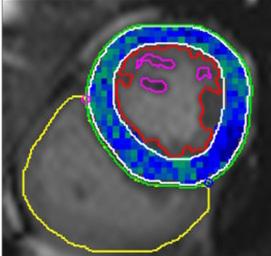

L’acquisition de cette manœuvre respiratoire et les analyses génèrent une cartographie de l’oxygénation myocardique. Rappelons que ces résultats sont dérivés d’une méthode qui n’a pris que quelques minutes à exécuter. La figure 4 présente quelques exemples des cartes obtenues.

Figure 4 : L’intensité du signal démontrant la réserve d’oxygénation du myocarde. A- Oxygénation myocardique globale chez un volontaire sain avec une augmentation globale et homogène de l’intensité du signal; B- Anomalie régionale (diminution de l’oxygénation du myocarde) chez un patient présentant une sténose coronarienne sévère; C- Réduction globale de l’oxygénation myocardique chez un patient qui souffre d’insuffisance cardiaque. La barre de couleur (à droite) fournit une légende pour les différences d’intensité du signal qui correspondent aux différences d’oxygénation myocardique. Les changements négatifs de l’intensité du signal sont mis en évidence par le bleu et le noir, ce qui représente une réponse d’oxygénation altérée, tandis que les changements positifs de l’intensité du signal sont mis en évidence par le vert, ce qui représente une réponse d’oxygénation saine.